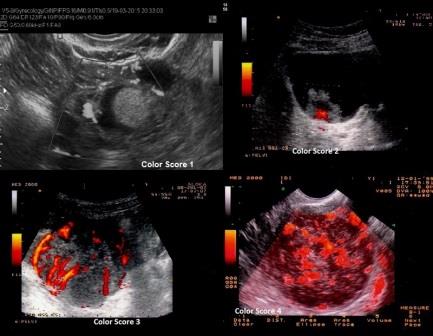

A margine credo possa essere utile ricordare come si calcola il Color Score. Esso rappresenta una valutazione della vascolarizzazione di una neoformazione annessiale stimata soggettivamente dal medico ecografista secondo una scala che va da 1 a 4:

- Color Score 1: assenza di flusso

- Color Score 2: presenza di pochi spots vascolari

- Color Score 3: presenza di una discreta vascolarizzazione

- Color Score 4: presenza di abbondante vascolarizzazione